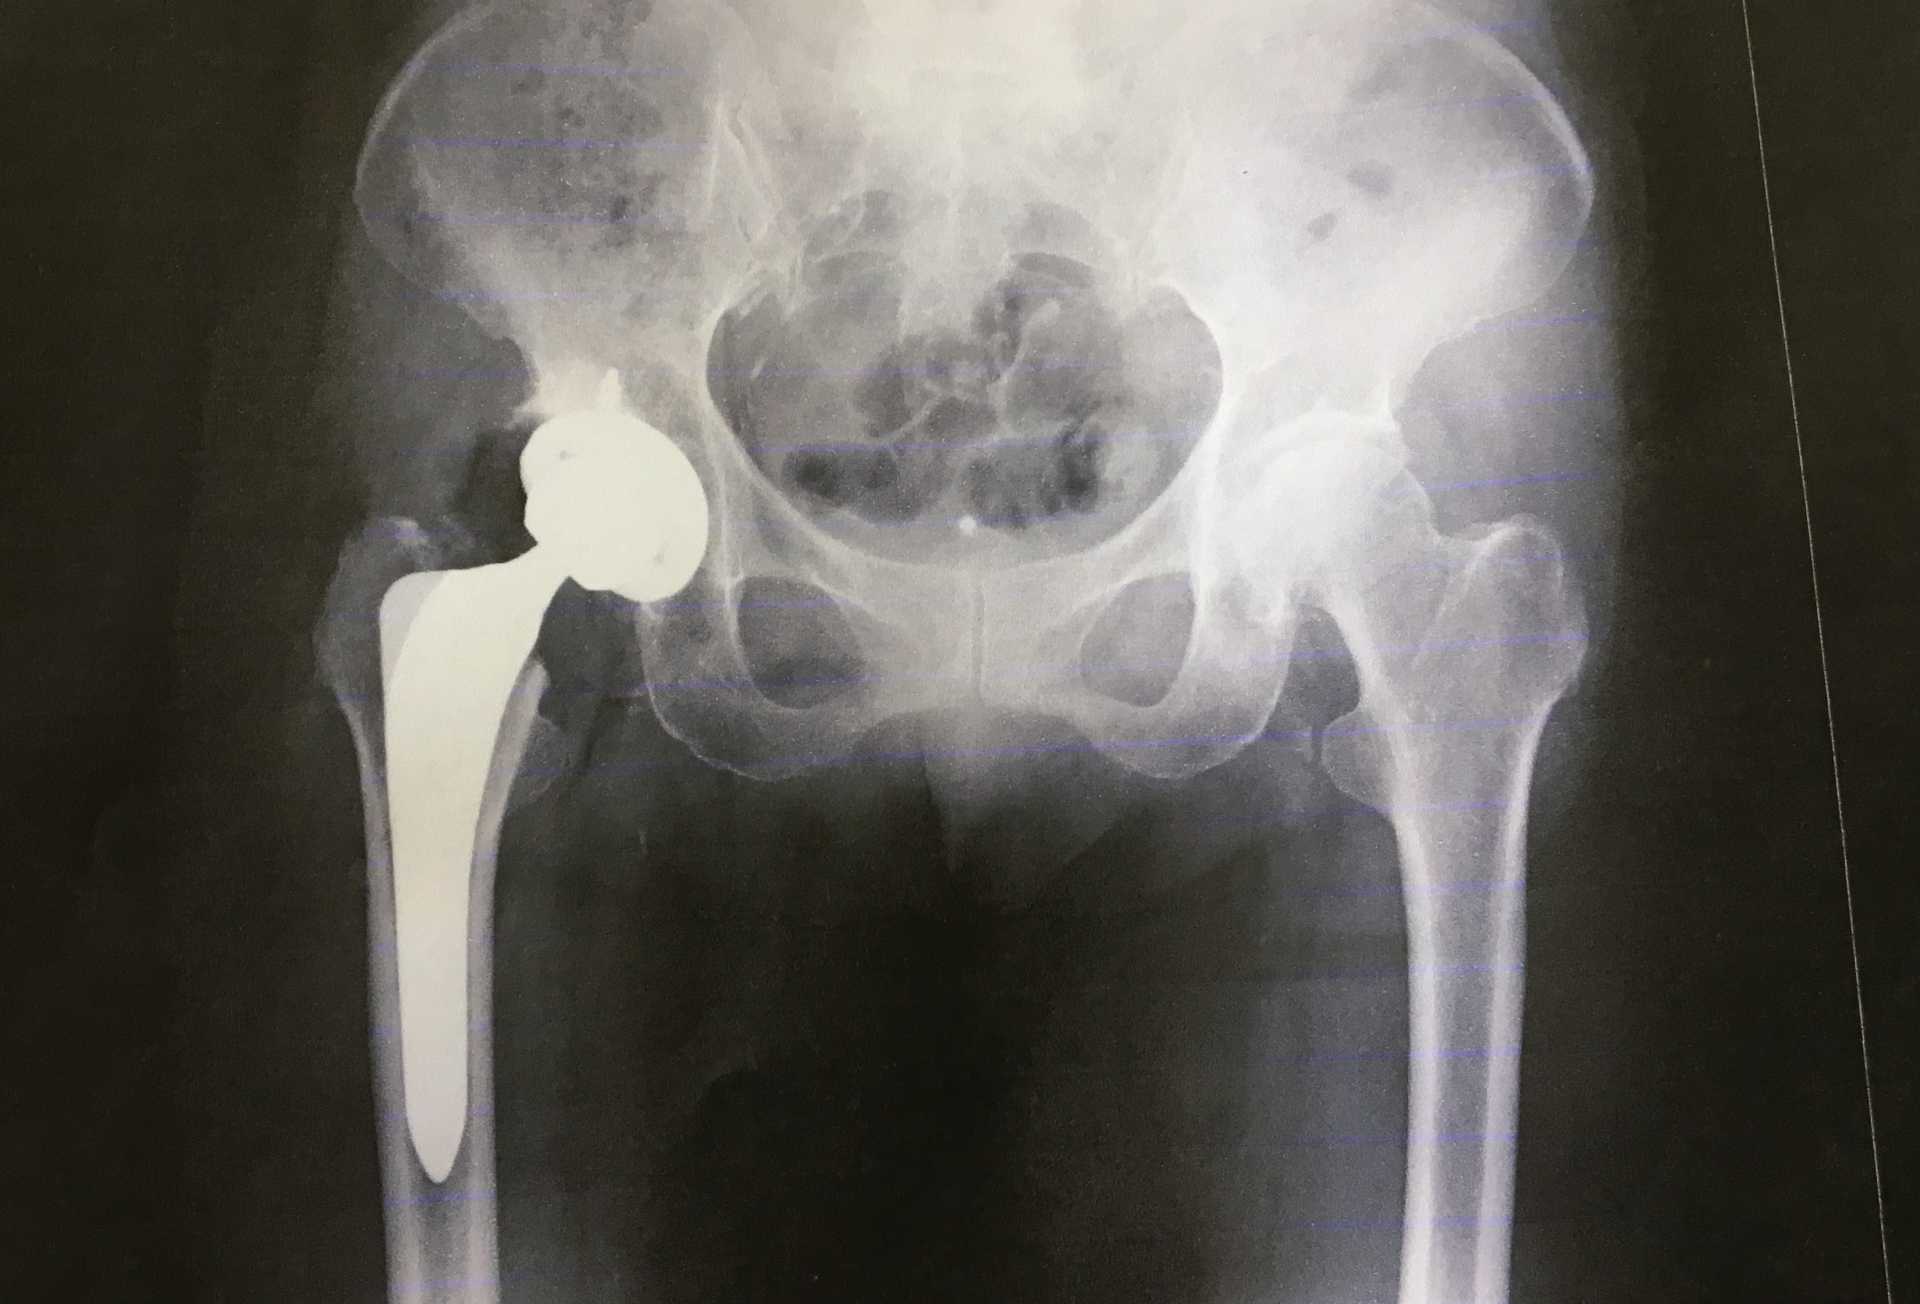

人工股関節全置換術、つまり関節形成術では、損傷したボールアンドソケット股関節を除去し、金属または耐久性のある合成材料で作られた人工股関節と置き換えます。